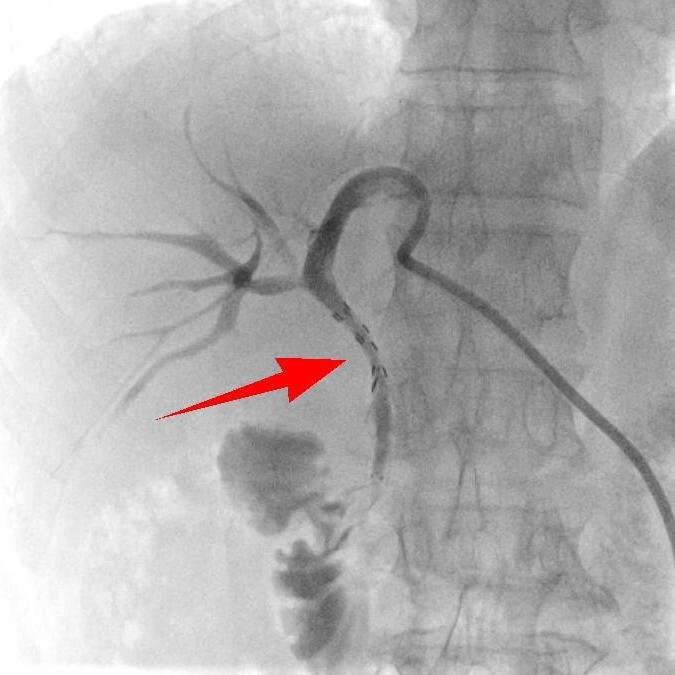

术后

“肚子不胀了,吃饭也香了!”术后第一天,杨大爷就感受到了变化。复查数据更是直观,术后第六天,各项指标基本恢复正常,黄疸彻底消退,老人面色红润如昔。如今,杨大爷已能正常生活,这场“高科技”手术的成功,不仅为他续上生命长度,更让基层患者在家门口就能享受到尖端医疗。